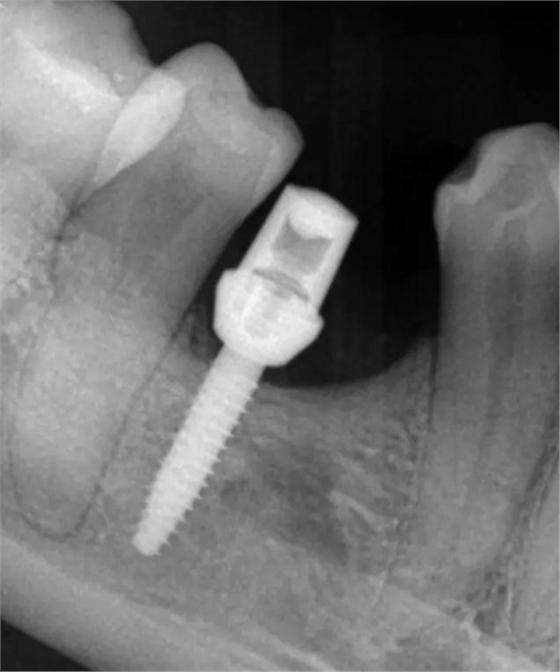

牙冠

4.jpg